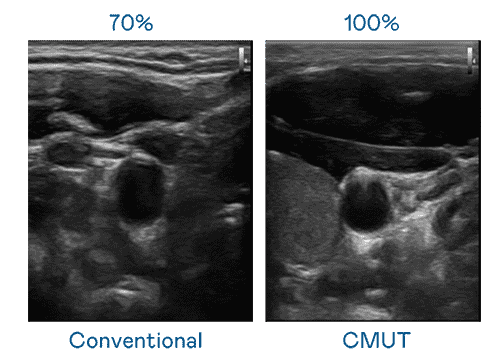

CMUT 技术是一种用电容式微机电元件来产生超音波讯号的技术。。。。与传统 PZT 压电式技术相比,,,CMUT 频宽增加 30%,,,,更宽频的超音波讯号让影像解析度大幅提升,,,,是实现高影像品质医疗超音波扫描、、促进精准医疗发展的关键技术。。

超音波影像的解析度高低,,,,首先取决于探头能发出的讯号频宽。。。。蓝狮在线 CMUT 可提供高清晰的超音波讯号,,提供高频宽、、、、高灵敏度、、影像纹理细节更高的超音波影像,,,协助医护人员缩短影像判读时间及利用精准的医疗影像进行诊断。。。。